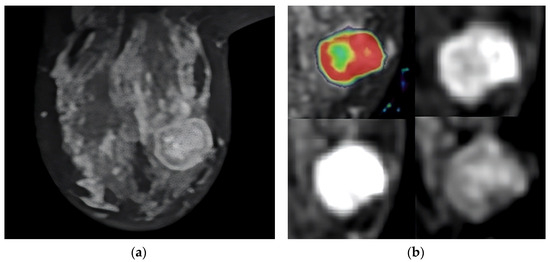

Figure 2.

T2-weighted MRI image that shows the tumor’s location in the axial slice (a). Perfusion mapping (red shows elevated perfusion) and progressive contrast change show washout in the tumor’s periphery (b).